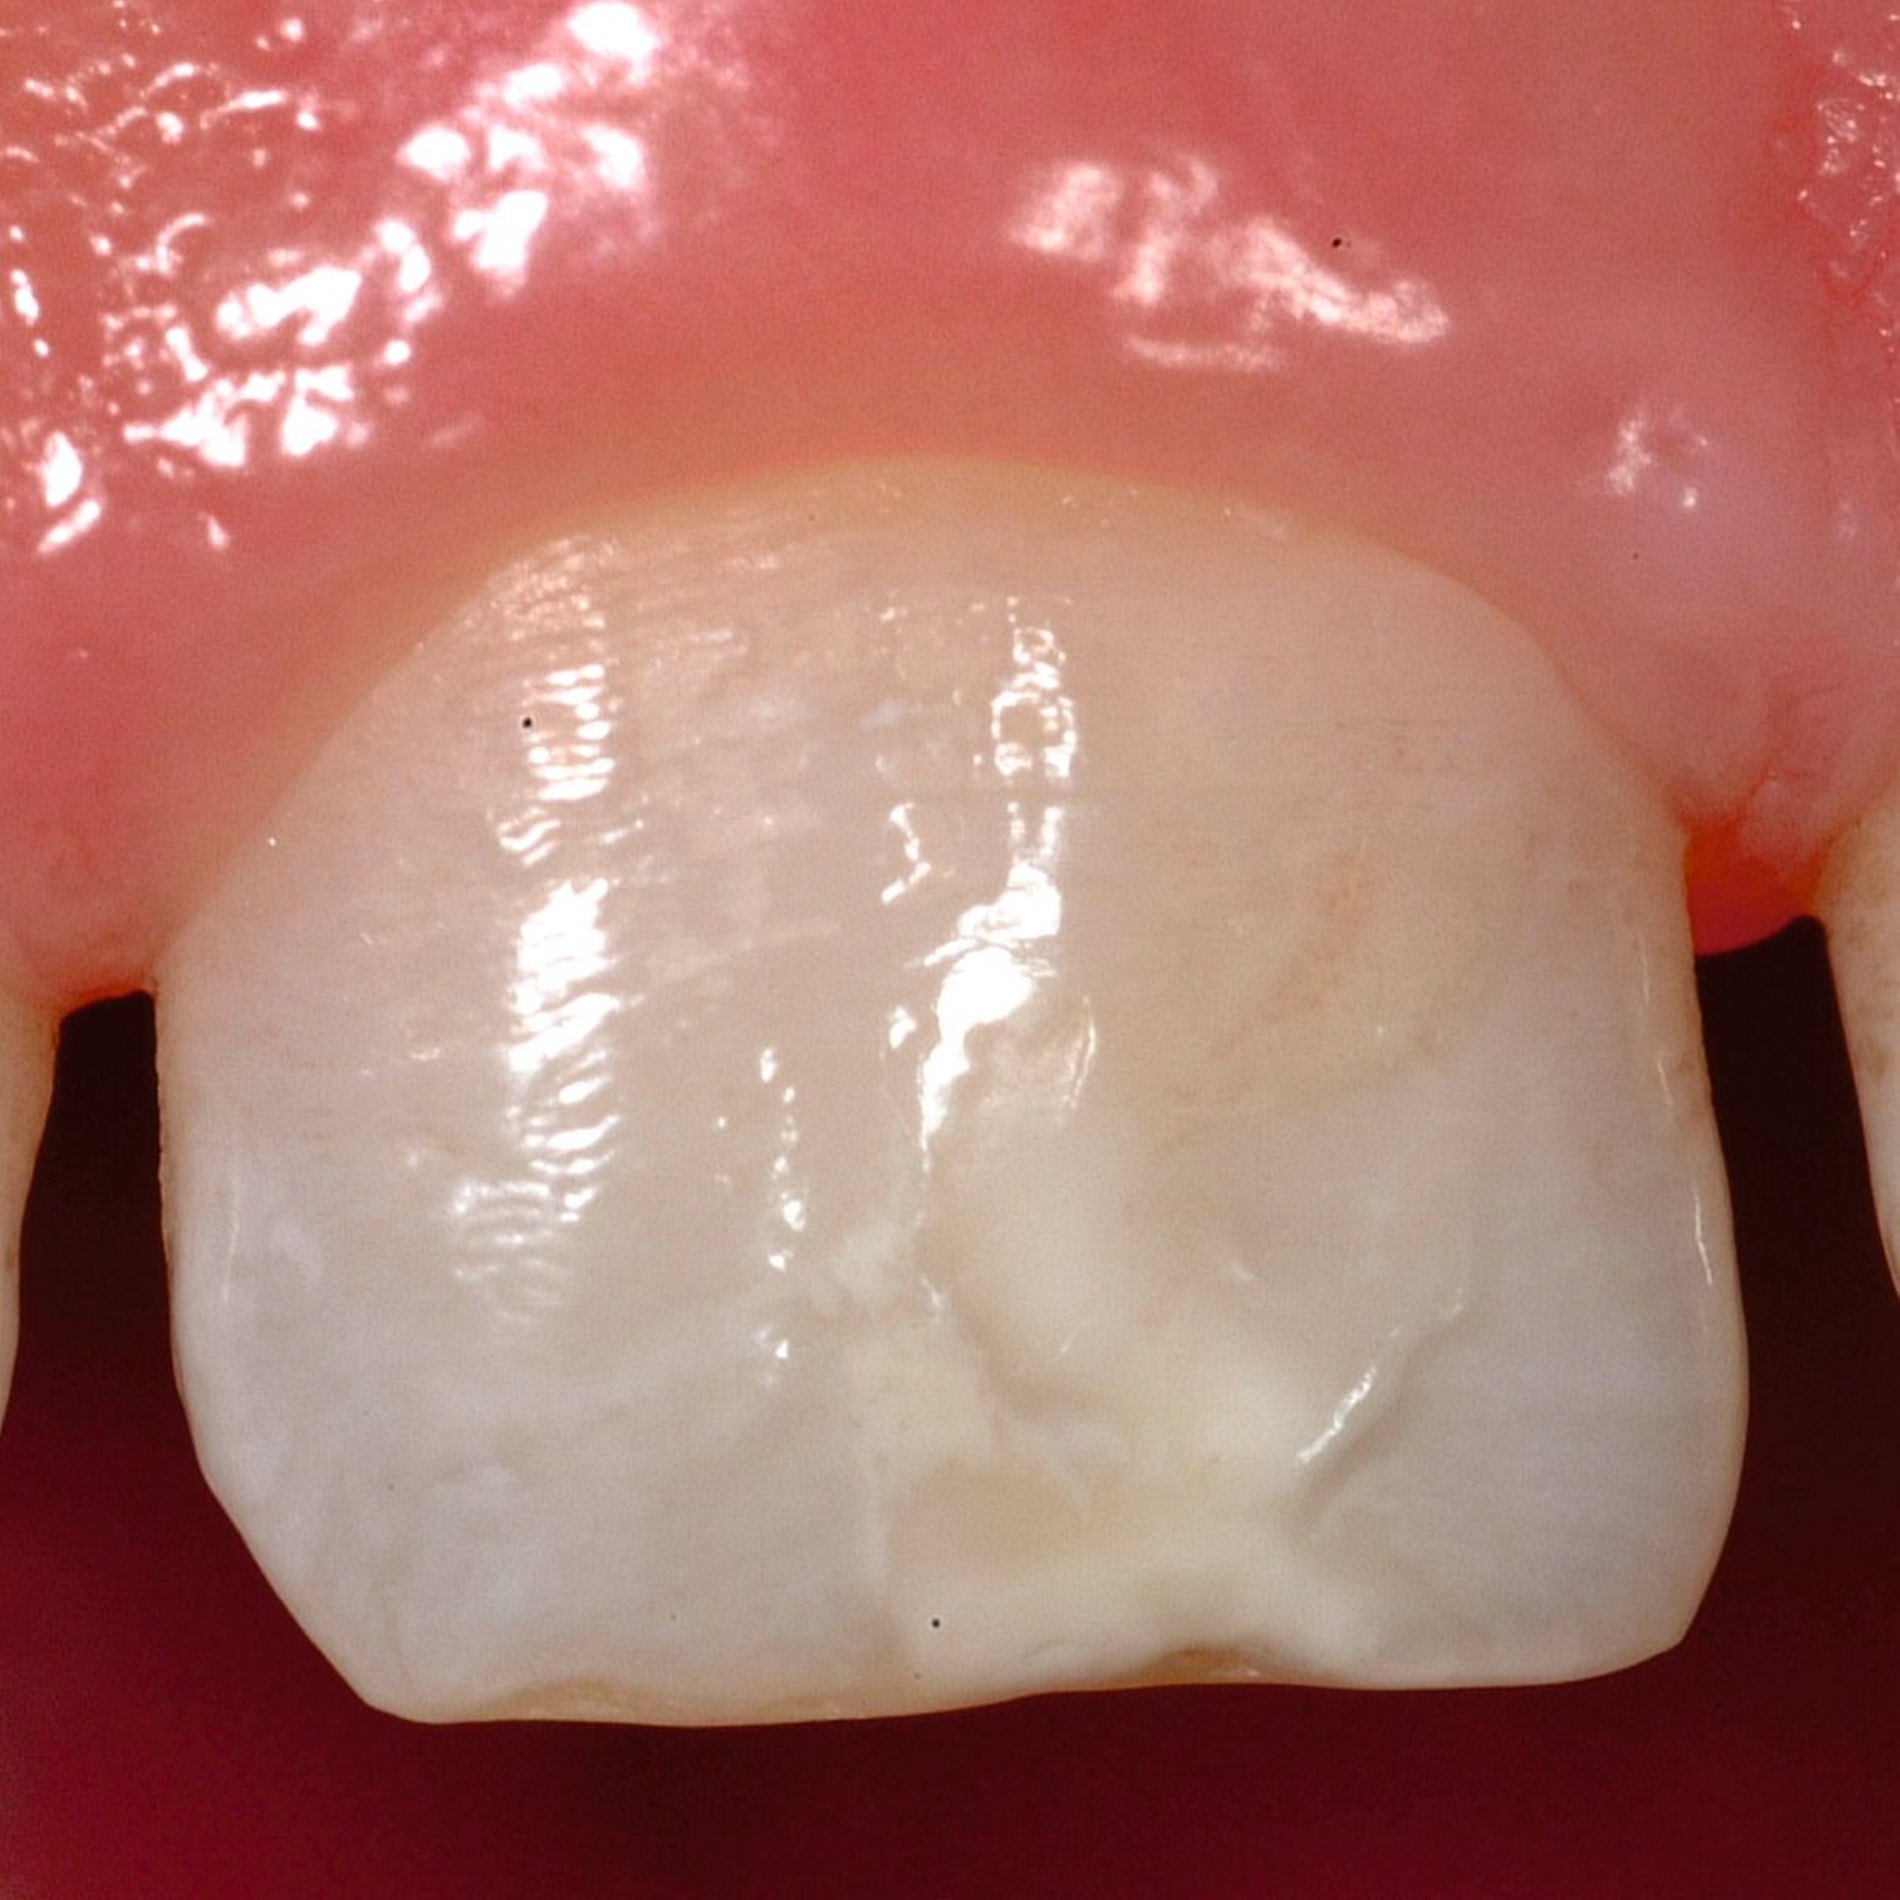

Das klinische Erscheinungsbild an bleibenden Zähnen zeigt typischerweise weißlich-gelbe bis gelblich-braune Opazitäten, die zumindest in einigen Bereichen durch eine scharfe Abgrenzung (engl.:„demarcated opacities“) zum gesunden Zahnschmelz charakterisiert sind (Abbildungen 3 und 4). Die abgegrenzten Hypomineralisationen befinden sich mehrheitlich im Bereich der inzisalen Kronenhälfte unabhängig von dem Auftreten an Front- oder Seitenzähnen. Die Ausprägung am Zahn kann dabei auf einzelne Areale oder Höcker begrenzt sein.

Für die Dokumentation und Klassifikation der MIH wurden verschiedene Systeme vorgeschlagen. Als historisch und veraltet gilt der (modifizierte) DDE-Index. Demgegenüber haben die Kriterien der EAPD – abgegrenzte Opazitäten (Abbildung 3 und 4), Schmelzeinbrüche (Abbildung 5), atypische Restaurationen (Abbildung 6) – mittlerweile die weiteste Verbreitung gefunden. Diese wurden 2003 erstmals zur Beschreibung der MIH auf empirischer Basis publiziert [Weerheijm et al., 2003] und den Jahren 2010 und 2022 im Rahmen der damaligen MIH-Workshops bestätigt [Lygidakis et al., 2010; 2022].